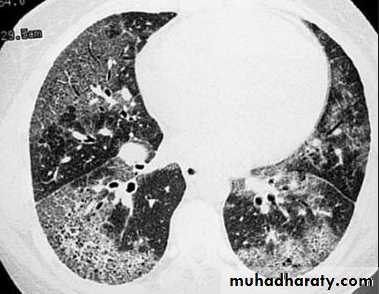

6- diffuse pulm. Disease.

Interstial lung disease